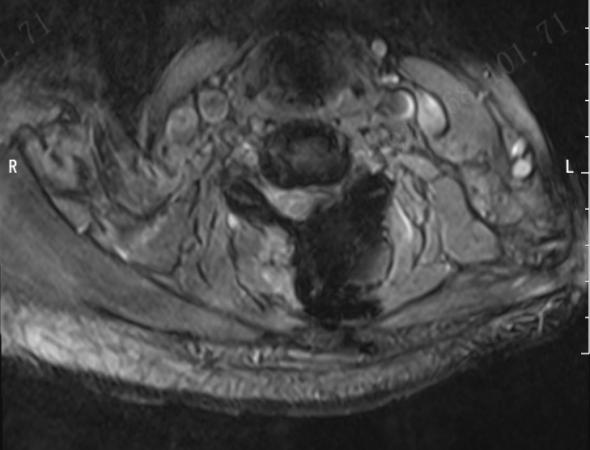

近日,济南市第四人民医院脊柱外科团队成功应用单边双通道内镜技术(Unilateral Biportal Endoscopy,简称UBE),为多位深受神经根型颈椎病折磨的患者实施了微创手术治疗。该技术的成功开展,标志着医院在脊柱微创领域取得了又一突破性进展,为本地及周边地区的颈椎病患者提供了一个更优、更精准的治疗选择。

神经根型颈椎病是由于颈椎间盘突出、骨赘增生等原因压迫了神经根,导致患者出现颈部疼痛,一侧上肢放射性麻木、疼痛、无力等症状,严重时甚至影响抓握、行走,生活质量大打折扣。

“UBE技术可以理解为给医生的眼睛和手装上了一双‘延长筷’,” 医院脊柱外科主任韩建龙教授形象地解释道,“通过两个仅约1厘米的微小切口,一个通道放入高清内镜,提供清晰放大的手术视野;另一个通道放入各种精密的操作器械。医生能够在清晰的视野下,精准地去除压迫神经的突出物或骨赘,彻底解放被‘卡压’的神经根,同时最大程度地保护了正常的肌肉组织和骨骼结构。”